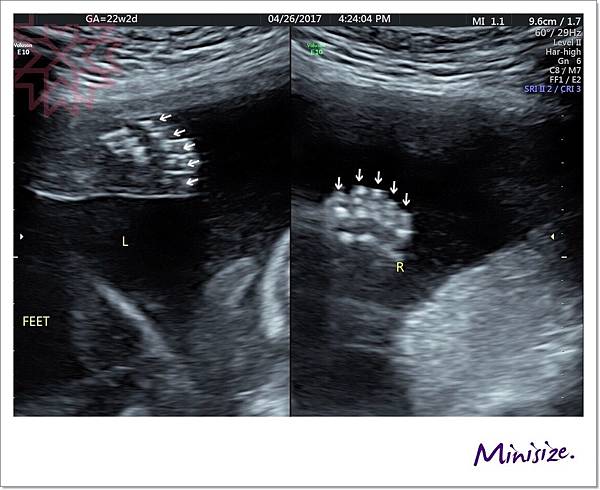

腳

腳趾就比較容易照啦

左右各是五隻腳趾頭

腳掌也發育良好